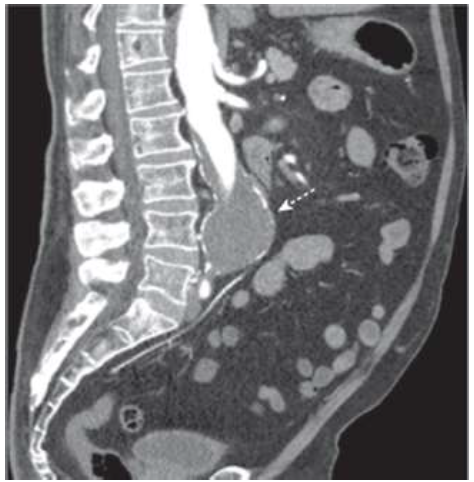

Paciente de 83 anos com dor abdominal, após ter sido submetido à uma US de abdome que revela massa é submetido à Angiotomografia que identifica a seguinte imagem.

Qual corte foi realizado e qual estrutura está assinalada?